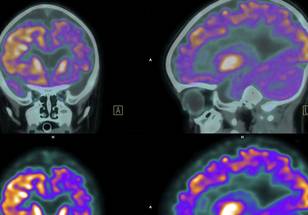

This case illustrates the evolving potential of immunotherapy in patients with advanced NSCLC, particularly those with brain metastases, a group typically facing poorer outcomes. Following WBRT, the patient achieved both intracranial and extracranial responses, with no disease progression for over six years. His overall survival currently stands at 87 months, and progression-free survival at 73 months, providing a significant example of extended remission in the context of metastatic NSCLC.

Researchers propose that the sequencing of WBRT and immunotherapy may be key to understanding this outcome. Brain metastasis in stage IV NSCLC is often associated with high morbidity and limited long-term survival, yet this case demonstrates that integrated treatments, including ICIs, could yield promising results for selected patients.